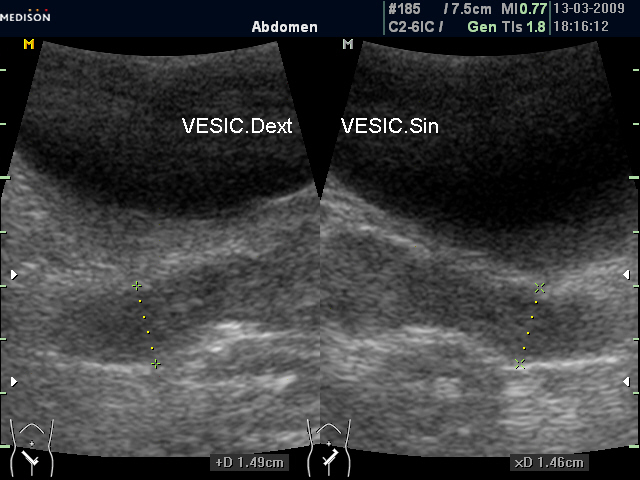

И еще "вдогонку", из вчерашнего. Правый СП 19,7 мм, левый - 23,3 мм.

Утолщенные "рыхловатые" немного асимметричные СП (ТА УЗИ)